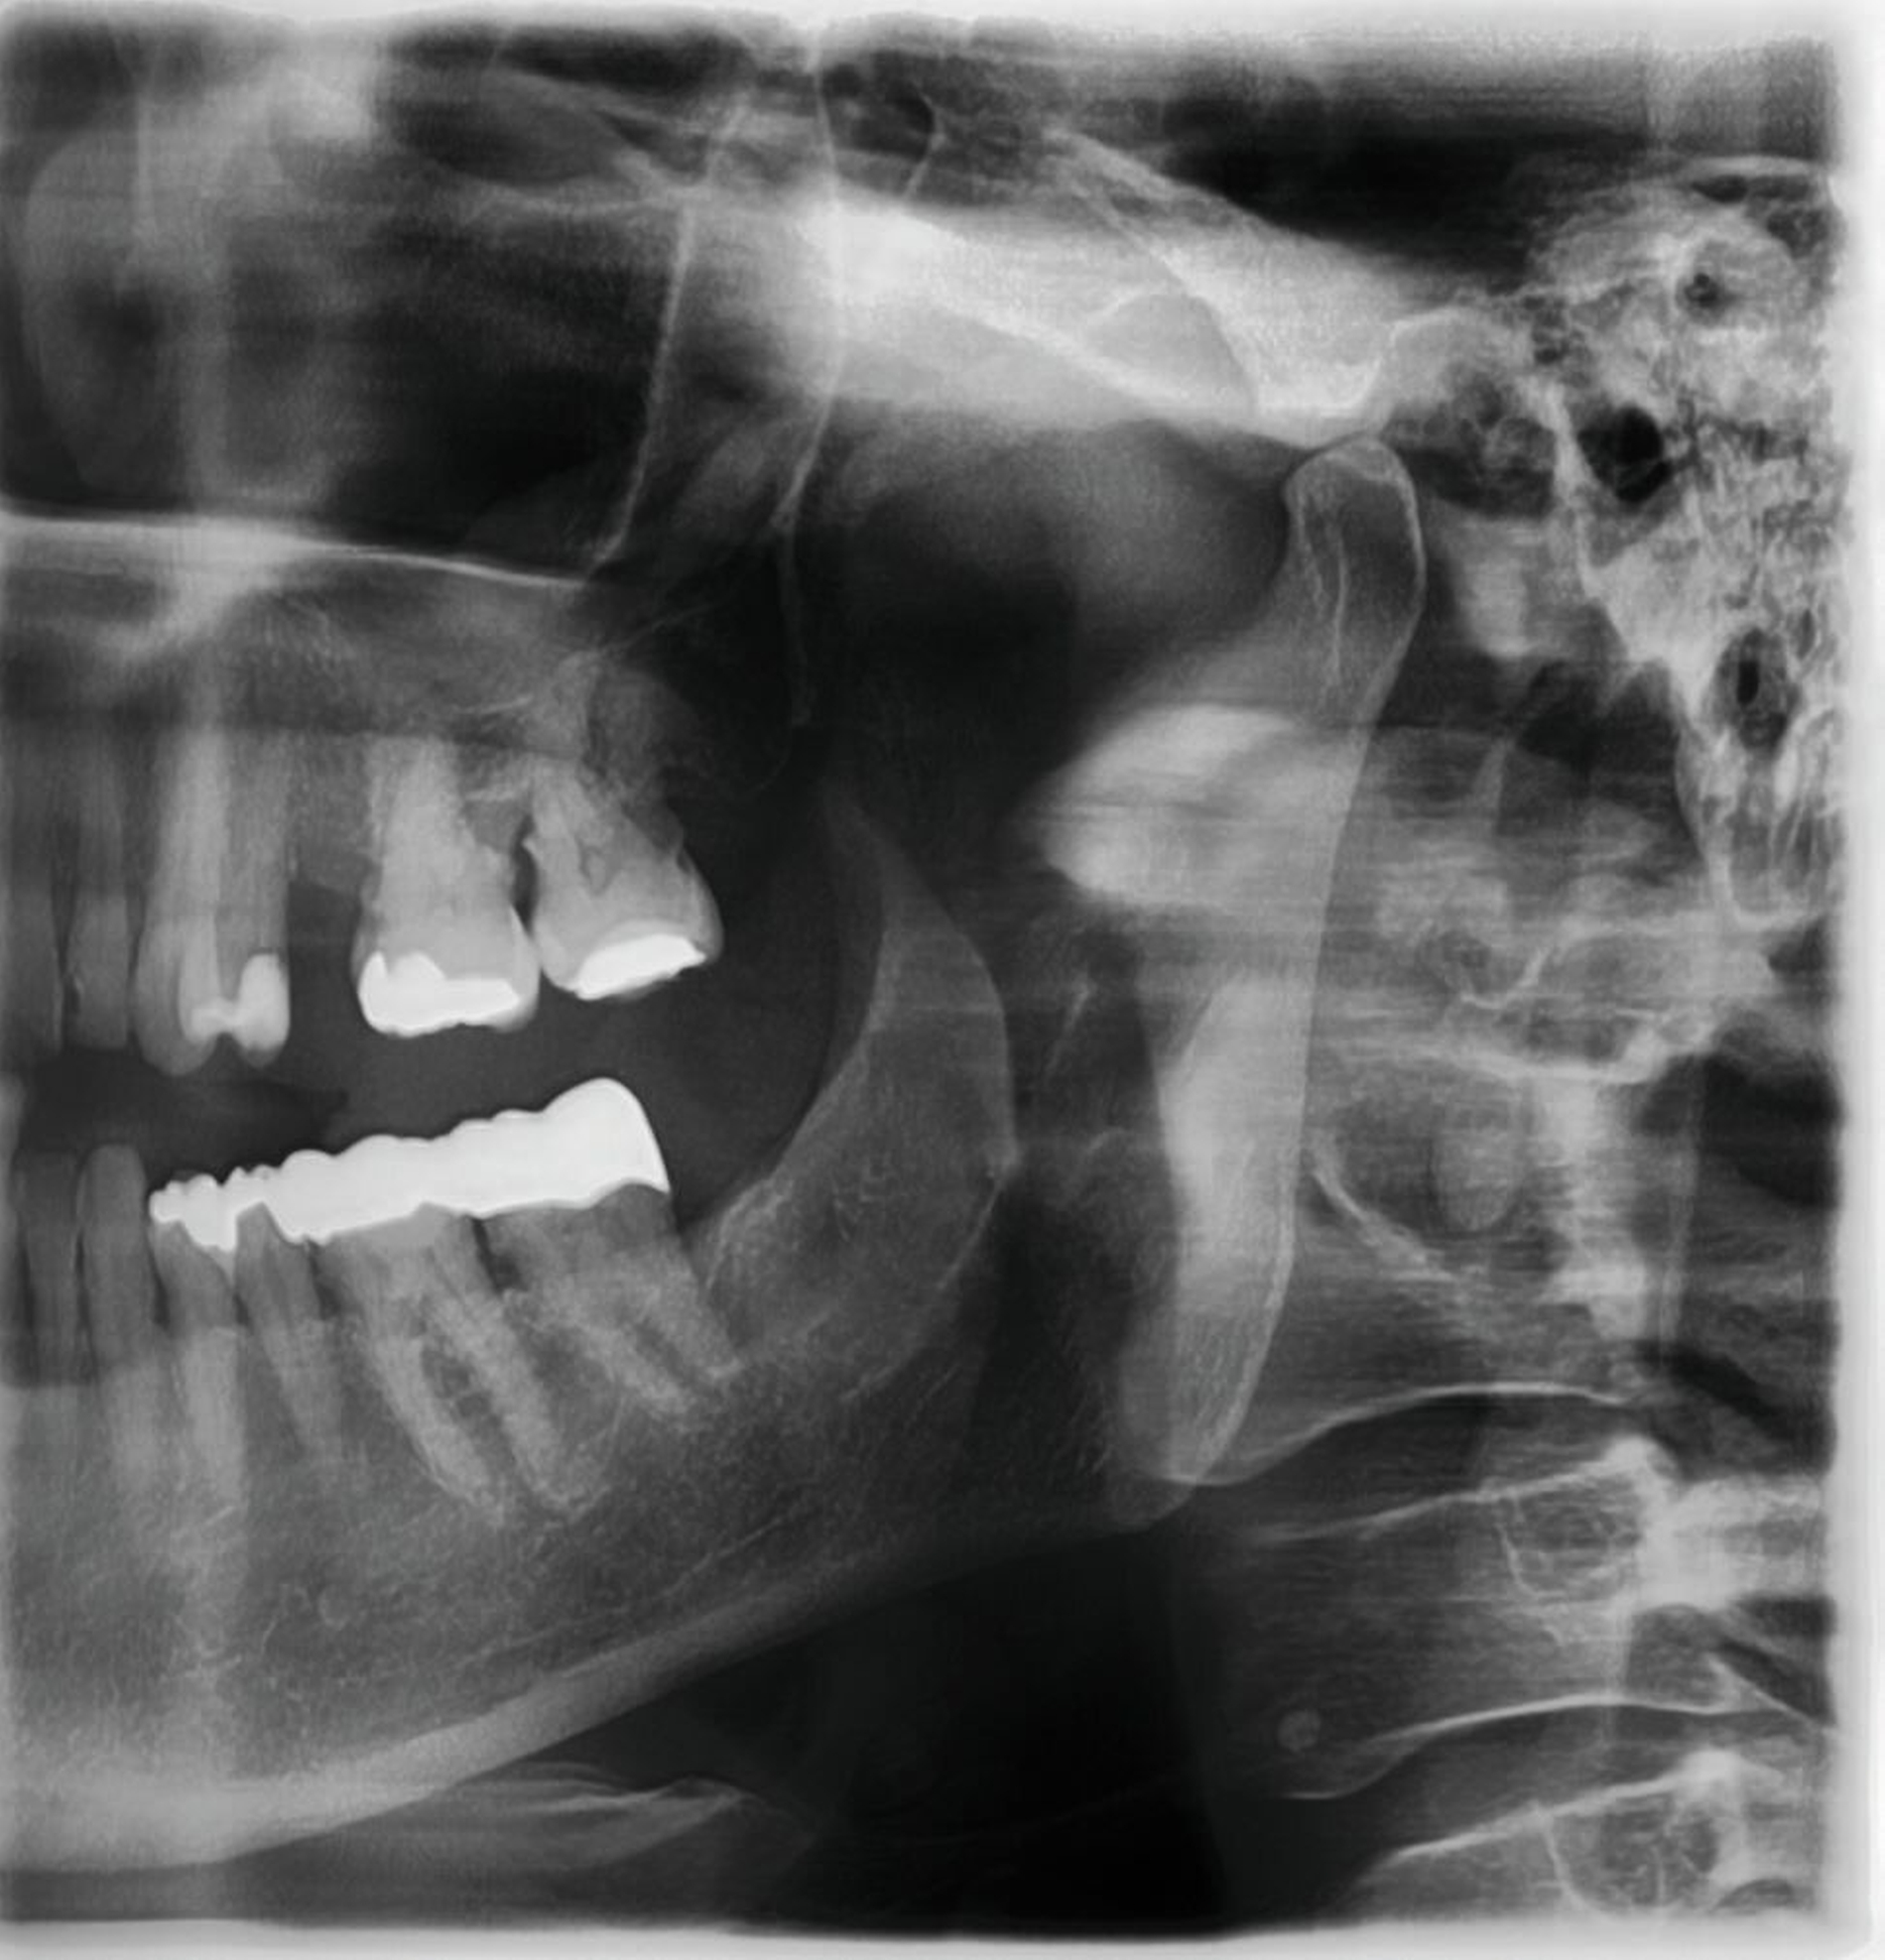

Das präoperative OPG zeigte einen generalisierten horizontalen und an den Zähnen 16 und 26 auch einen vertikalen Knochenabbau, Konkremente insbesondere im zweiten und im dritten Quadranten und in der Unterkieferfront, einen Füllungsverlust an 22, eine regelrechte Wurzelkanalbehandlung an Zahn 25, aber keine weiteren Auffälligkeiten in den umgebenden radiologischen Strukturen (Abbildung 2). Unter antibiotischer Abschirmung wurde der nekrotische Knochen einschließlich des Zahnes 25 bis zum vitalen, durchbluteten Gewebe in Lokalanästhesie abgetragen (Abbildung 3). Der Wundverschluss erfolgte mittels eines Dehnungslappens durch Periostschlitzung (Abbildung 4). Es folgte eine detaillierte Instruktion zur postoperativen Wundschonung. Eine Röntgenkontrolle wurde postoperativ durchgeführt (Abbildung 5).